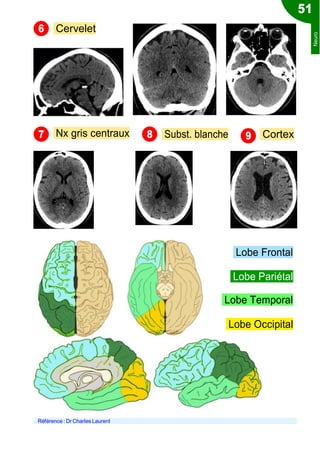

Check-list lecture du scanner

1 Ligne médiane? Foramen magnum libre?

Taille des ventricules et des sillons

Liquides péri-cérébraux Tronc cérébral

3

4

Neuro

Cervelet

Nx gris centraux Subst. blanche Cortex

Lobe Frontal

Lobe Pariétal

Lobe Temporal

Lobe Occipital

Référence : Dr Charles Laurent